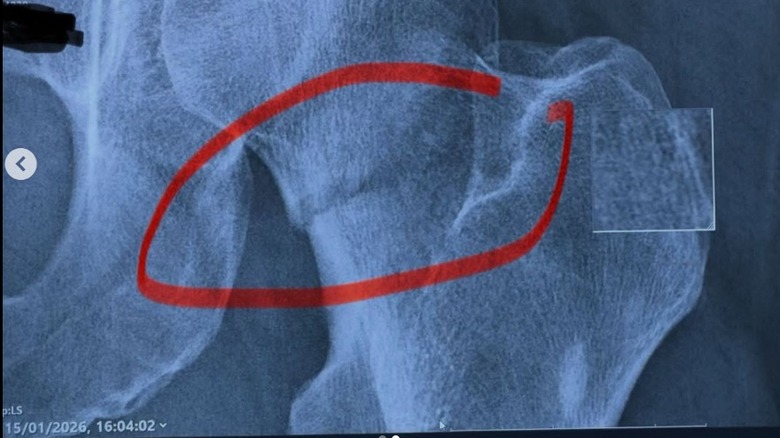

Morgan said that he "tripped on a small step," ultimately fracturing the top of his femur. (This means he has something in common with athlete Tony Hawk, who also broke his femur several years prior to Morgan's incident.) The break was extensive enough to warrant hip replacement surgery, a procedure that's common in both the United Kingdom and the United States. (Surgeons in the UK perform more than 100,000 hip replacements annually; in the U.S., the yearly figure soars to more than 500,000.)